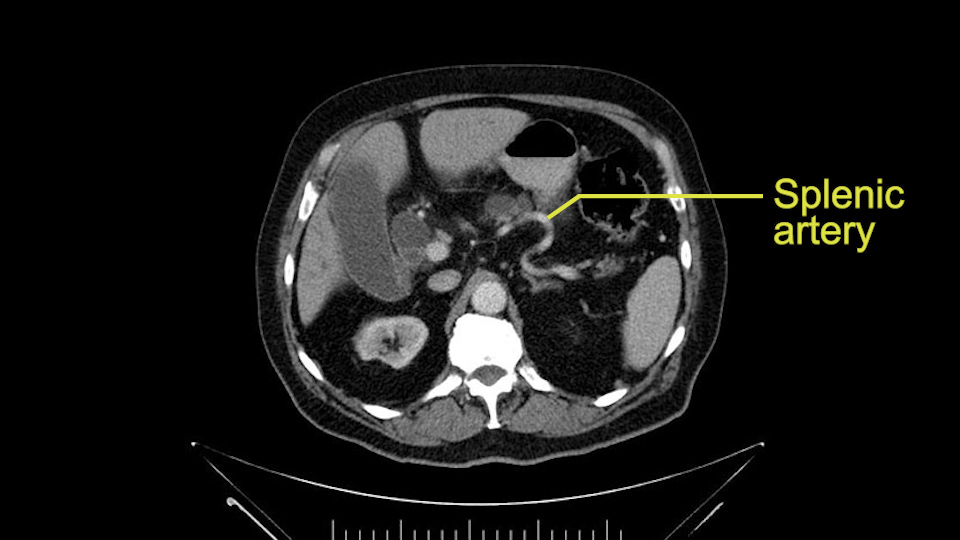

Then you look for anomalies. The one you worry about the most doing a Whipple is a replaced or aberrant right hepatic artery coming off the SMA at its origin. So again, find the SMA. You can find it because the renal vein goes through it. Follow it up, up-up-up. Nothing coming off of there that I can see here. Nothing coming off of it, nothing coming off of it and just to confirm it, look at the celiac trfurcation. There’s the celiac, there’s the bifurcation, there's the splenic artery, hepatic artery. Make sure there’s a right, which there is here. The right usually goes under the bile duct: important when you’re going around the bile duct to do a Whipple. A replaced right goes under the portal vein and the bile duct way over here on the right. That’s about it.